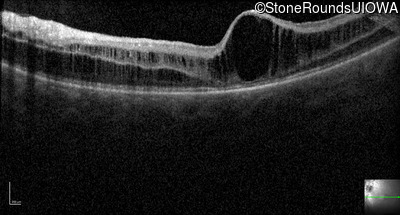

Optical Coherence Tomography - Right - 10/40

Exemplar / OCT Stack